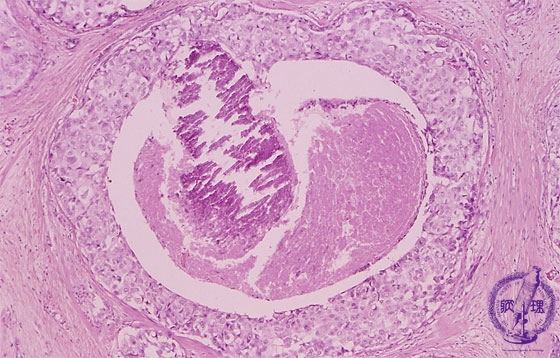

- ★(5)noninvasive carcinoma (comedo type)

Microscopic image(HE stain, high power view):Large carcinoma cells piled up to several layers filling ductal lumen (arrow). Central necrosis and necrotic calcification (dotted line) are also apparant.